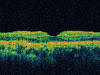

La tomografía de coherencia óptica (OCT) revelaba zonas hiperreflectantes correspondientes a las cicatrices sin edema macular (fig. 4).

Fig. 4: Zonas hiperreflectantes sin edema macular en la OCT.